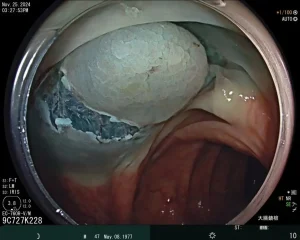

我們迎來豐田之山診所在手術房的第一台‘’黏膜下腫瘤切除術‘’。

這主要是切除大的胃腸道息肉或者黏膜下腫瘤。

葛振瑜醫師在高雄長庚醫院施行ESD的經驗豐厚。

當劉建宏醫師的找到第一個合適的患者,‘’一‘’就開始了。

在麻醉醫師的配合下,術式進行順利。世間又少了一個大腸癌的候選人。